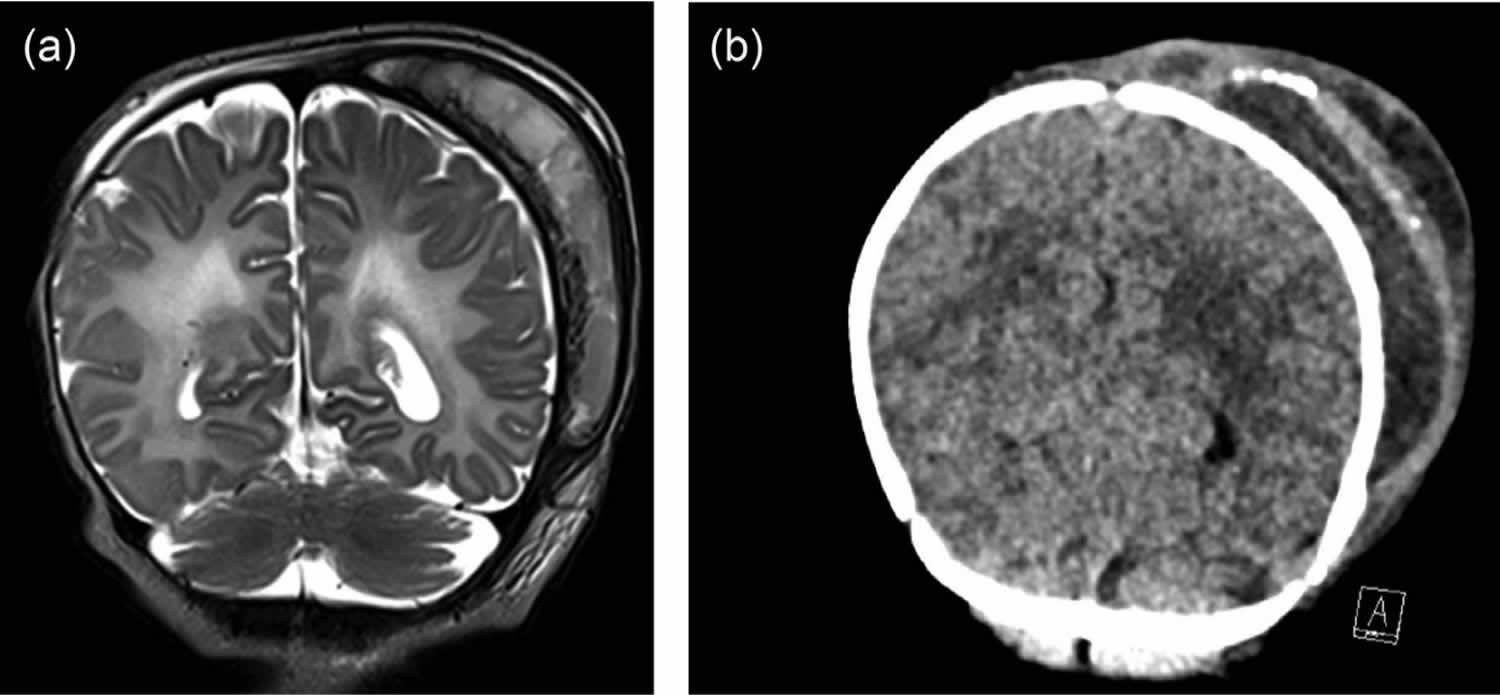

[Source 25 ]Figure 9. Cephalohematoma with abscess

Footnotes: A 4-week-old male term infant presented with 1 day of irritability and fever. The perinatal course had been uncomplicated following a spontaneous vaginal delivery. There had been no instrumental assistance or intrapartum fetal scalp electrode monitoring during parturition. Maternal intrapartum penicillin was given for group B streptococcal prophylaxis and the newborn

was noted to have a large cephalohematoma at birth. A septic screen performed prior to administration of antibiotics revealed a urinary tract infection (UTI) with pure growth culture of Escherichia coli (>100 x 109 CFU/mL), susceptible to gentamicin and ceftriaxone. The initial cerebrospinal fluid (CSF) revealed a normal cell count on microscopy (nucleated cell count 2 x 106/L), normal biochemistry and negative culture. The blood culture was also negative, white cell count (WCC) was 5.7 x 109/L and C-reactive protein (CRP) was 77.4 mg/L. Cranial ultrasound showed a lentiform 8.9 x 6.9 cm collection consistent with a large uncomplicated cephalohematoma. Following 4 days of therapy with sensitive antibiotics, he continued to have persistent fever and irritability, coverage was broadened to meropenem and he was transferred to a tertiary paediatric center for further investigations. (a) Coronal view of magnetic resonance imaging (MRI) of the brain with contrast demonstrates the large cephalohematoma over the left parietal convexity. On day 12 of admission, the cephalohematoma became warm and fluctuant with associated elevated white cell count (WCC) of 23.6 x 109/L and C-reactive protein (CRP) of 118 mg/L. Purulent fluid was percutaneously aspirated with subsequent incision and drainage under general anesthesia. The aspirate and operative swabs cultured Escherichia coli, with an identical susceptibility profile to the initial urine specimen. Another incision and drainage was performed 3 days later due to reaccumulation. Following this, the child defervesced and improved markedly. (b) Coronal view of the a computerized tomography (CT) scan without contrast of the head after two surgical debridement procedures. A persistent fluid collection at the left parietal scalp/bone shown is in keeping with a residual cephalohematoma. Superficial to this is a hyperattenuating rind containing multiple coarse foci of calcification demonstrating visible periosteal reaction. Within the soft tissue edema, there are numerous loculations of fluid with pockets of gas.